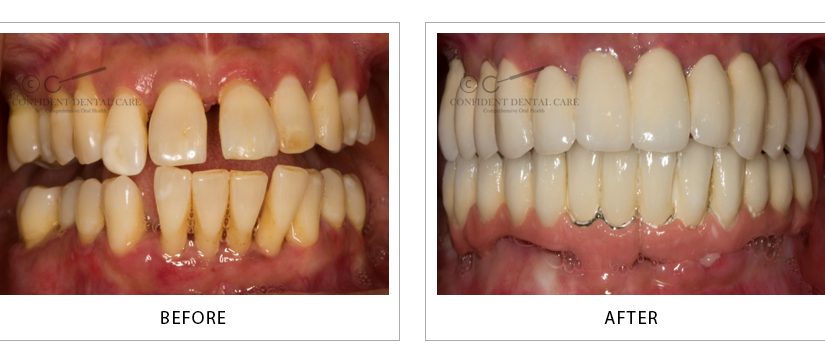

Implant Support Denture